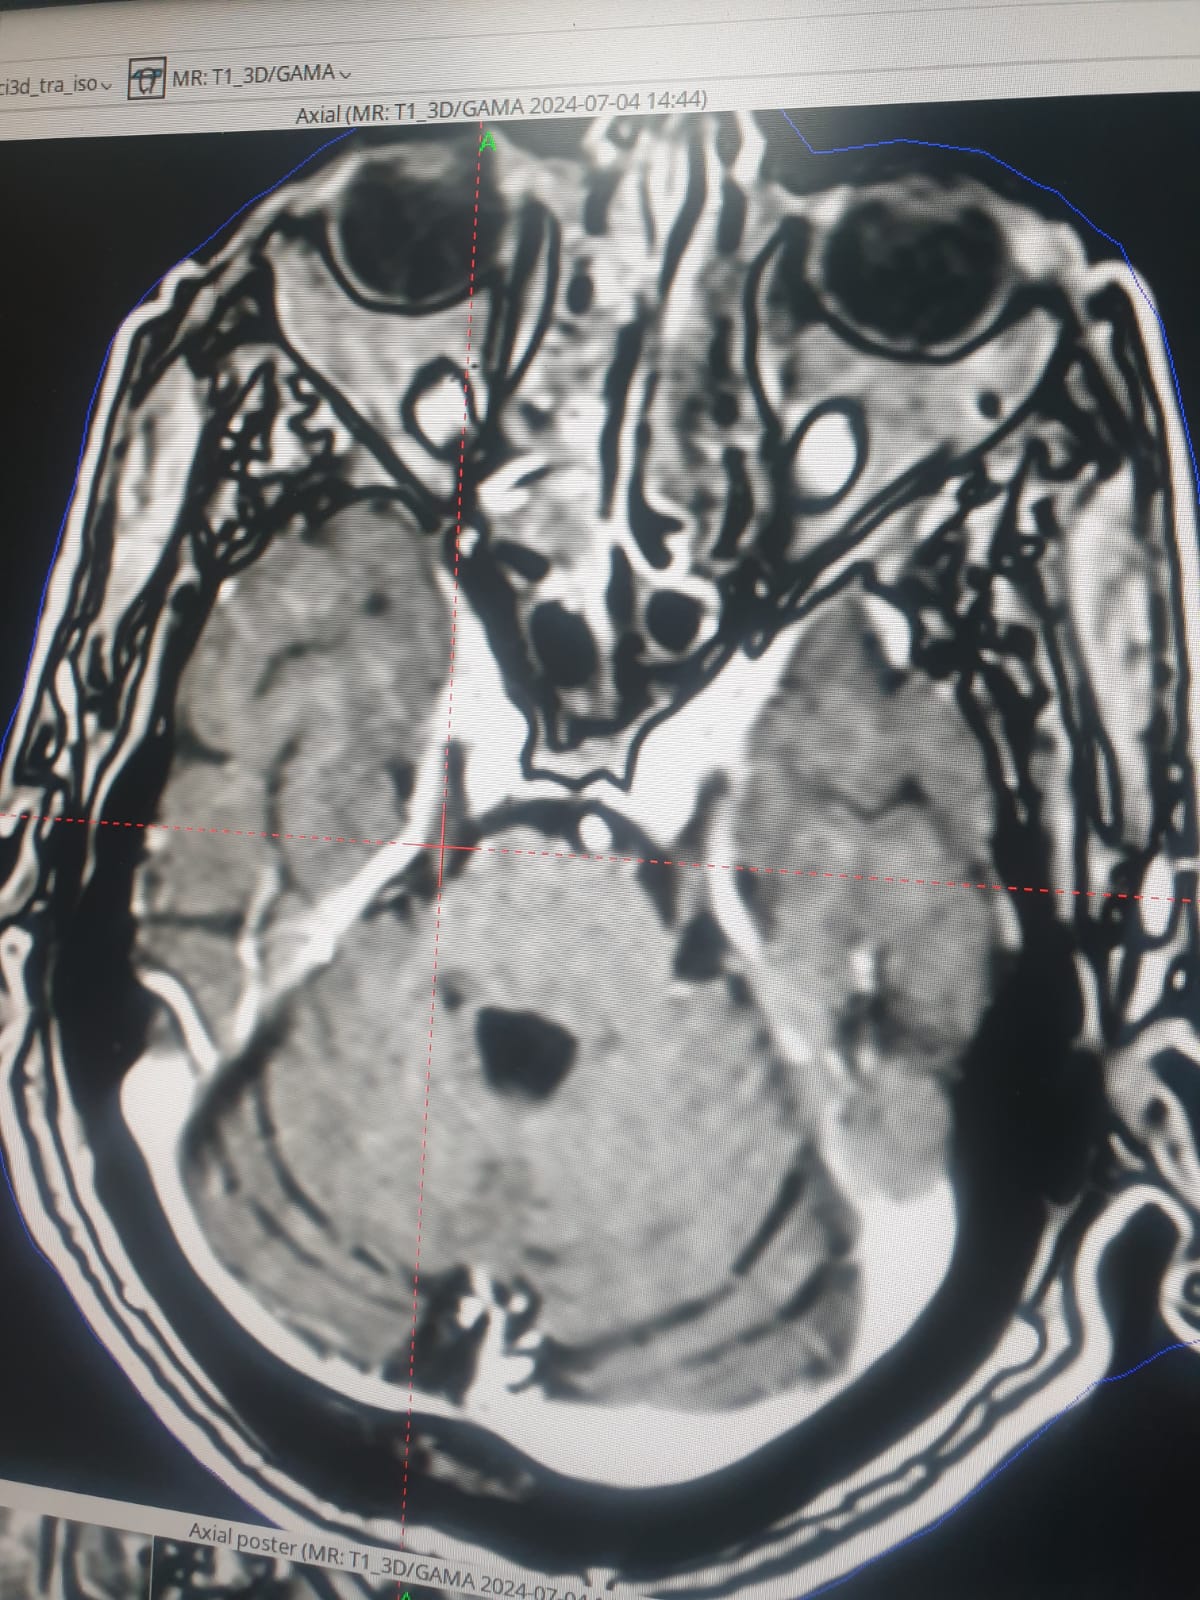

A trigeminal nerve tumor is treated with Gamma Knife radiation.

Professor Dr. Adil Ameer Jassim Mohammed, a faculty member in the Surgery Department at Al-Nahrain College of Medicine, treated a trigeminal nerve tumor using the latest technique, Gamma Knife radiation.